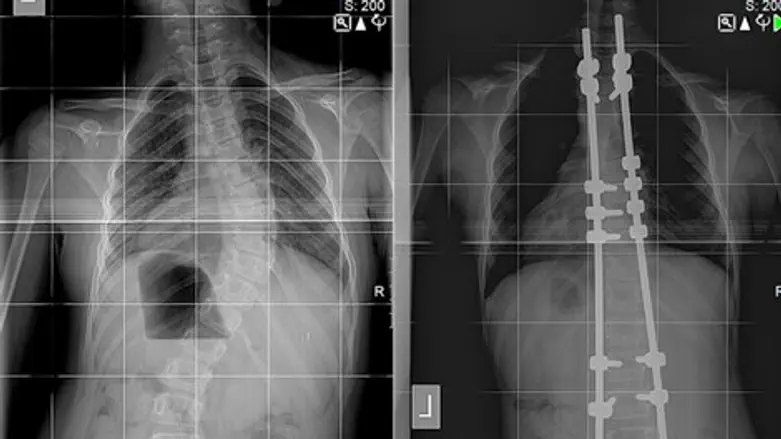

ילדה בת 8 נותחה במרכז הרפואי אסף הרופא בשיטה חדשנית לטיפול בעקמת.

הילדה נותחה על ידי פרופ' יגאל מירובסקי, דר יורם אנקשטיין ודר יוסי סמורג'יק, במהלך הניתוח הושתלה בגופה מערכת SHILLA™ Growth Guidance, אשר מיוצרת על ידי חברת מדטרוניק.

מערכת SHILLA היא טכנולוגיה המאפשרת לטפל בעקמת ילדים בני פחות מ- 10, שהשלד שלהם טרם התבגר, ואשר אובחנו עם התהוות מוקדמת של עיוותים חמורים מתקדמים בעמוד השדרה. הודות למערכת החדשה ניתן להציע ניהול אפקטיבי וביצוע תחזוקה של התיקונים בעמוד השדרה, במקביל לצמיחה הטבעית של הילד לטיפול אפקטיבי בעקמת ללא צורך בניתוחים חוזרים.

מערכת SHILLA עושה שימוש בברגים מיוחדים שאינם ננעלים וממוקמים בקצוות מוטות המבנה. מאפיין מיוחד זה מאפשר למוט להחליק דרך ראשי הבורג כאשר עמוד השדרה של הילד גדל ובמקביל לספק תיקון של הפגם בעמוד השדרה. התקנת הברגים נעשתה בעזרת מערכת ניווט שהינה מונחת מחשב ובעזרת מכשיר O ARM, שמאפשר סריקה תלת מימדית על שולחן הניתוחים. השימוש במערכות אלו מאפשר התקנת השתלים ללא חשיפה מלאה של חוליות עמוד השדרה ובכך נמנעה הפגיעה בצמיחה התקינה של עמוד השדרה.